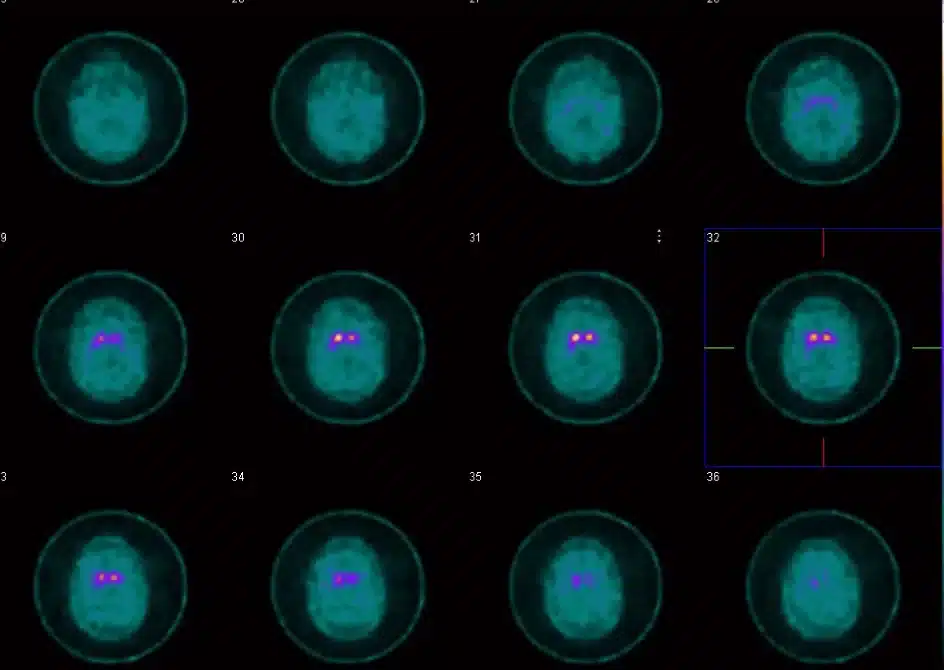

Everything culminated last week when I went to Mount Sinai for an MRI and a DAT Scan (a Dopamine Transmitter Scan, to help confirm Parkinson’s). For the DAT Scan, they injected dye into my blood that attached itself to dopamine so they could see it light up in my brain (Parkinson’s is the progressive loss of dopamine).

We Zoomed with the doctor yesterday, and as she explained, that image in the middle on the right shows the Dopamine receptors in my brain. The one on the left looks like a comma or an eye with a teardrop; the one on the right is missing its teardrop. That’s actually the left side of my brain and it’s missing those Dopamine receptors, hence the rigidity and tremor on my right side.